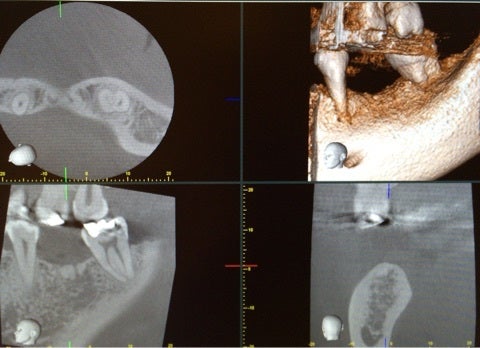

それでは当院でのインプラント手術の例です。

患者様は左下の奥歯が欠損してしまい、しっかり食事を摂りたいという希望で無痛治療でのインプラント手術を選択されました。

術前に綿密にシミュレーションを行っていたものとほぼ同じ位置に埋入されていることが確認できます。

今回は埋入手術の話ですが、当院では上記にお話ししたインプラントの成立要件を全て確認し、シミュレーションを行い手術を行っています。